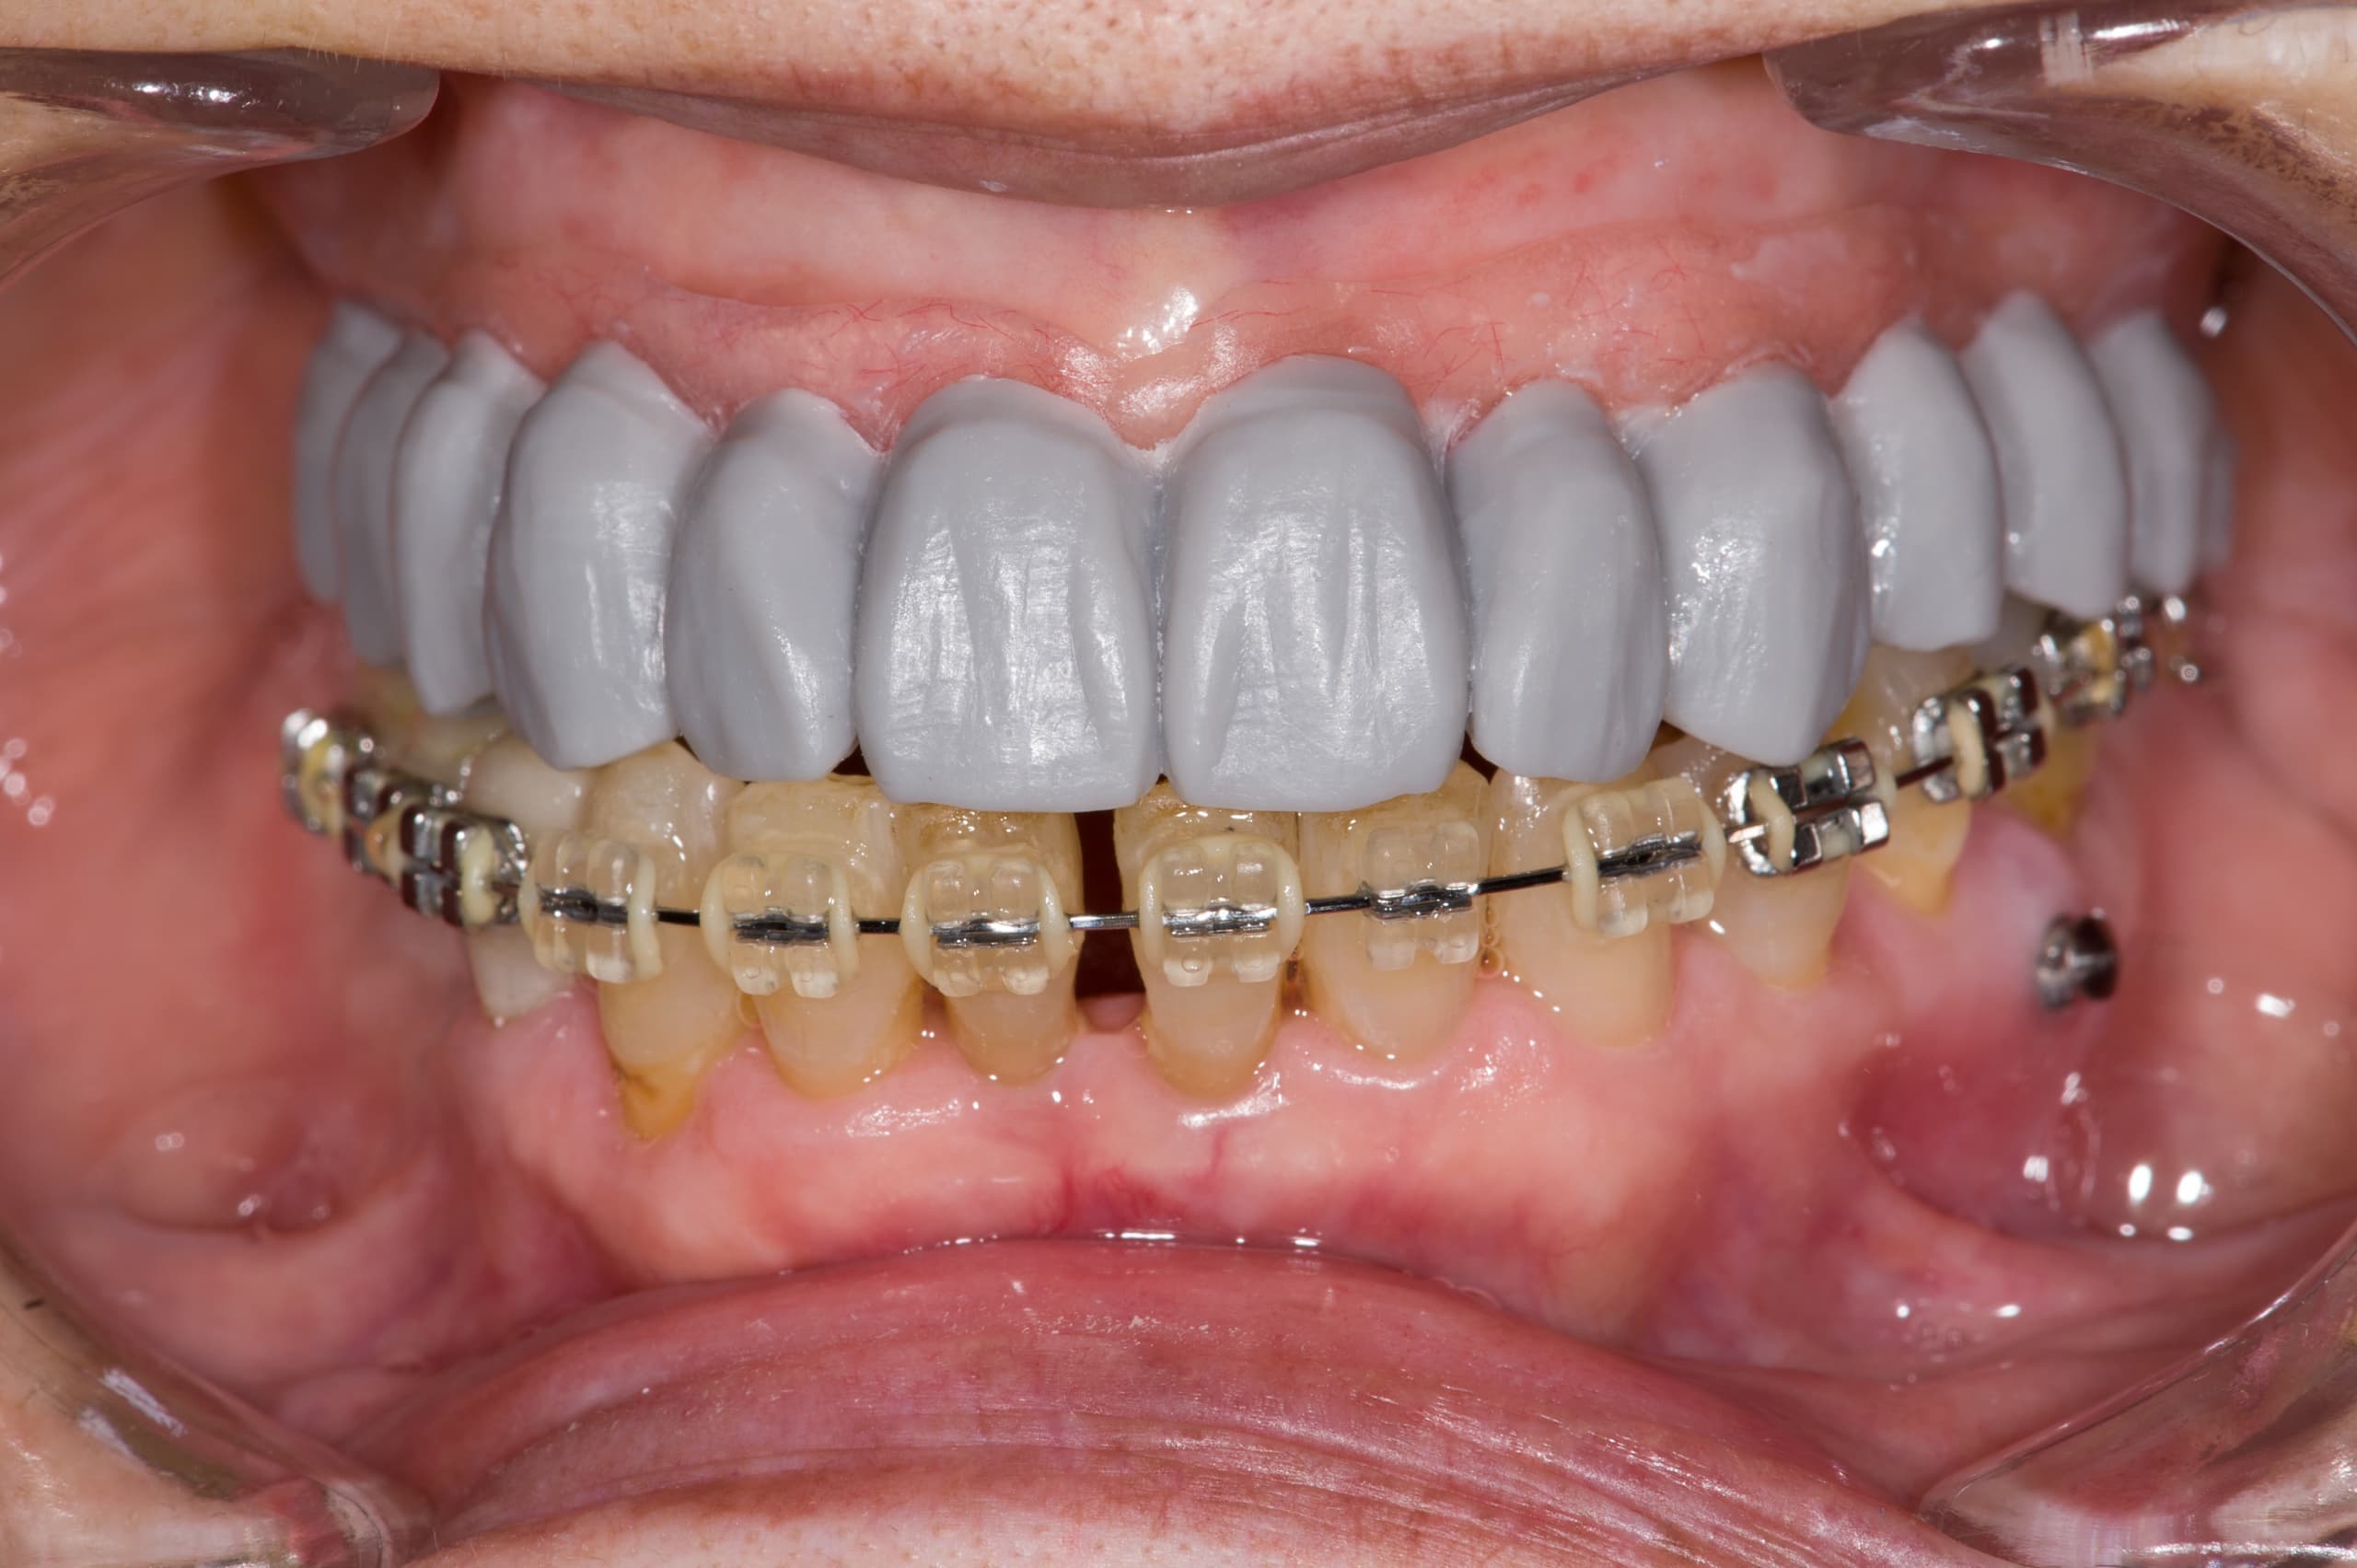

変更3

歯をなるべく削らずに

最新治療法・最新材料を導入し審美治療に対する患者様のご期待に添えるよう日々診療にあたっております。